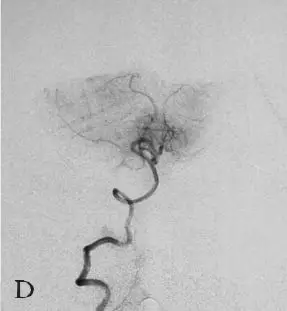

D:右侧椎动脉造影;

E:左侧椎动脉造影。

DSA:急诊全脑血管造影提示右侧颈内动脉发出变异的原始三叉动脉,该三叉动脉直接向右侧小脑前下动脉(AICA)供血区域供血,在原始三叉动脉自颈内动脉发出部位可见1枚梭形动脉瘤(图18-1B、C),右侧椎动脉发育较差,仅供血小脑后下动脉(PICA)区域(图18-1D)。右侧小脑前下动脉(AICA)未见显影,可见基底动脉发出的部分回旋支显影(图18-1E)。其余血管造影未见明显异常。

DSA:急诊行全脑血管造影提示基底动脉下段可见1枚形态不规则囊性动脉瘤(图18-3B)。三维重建后提示基底动脉下段开窗畸形,动脉瘤瘤颈位于开窗近段分叉处,瘤顶有子囊(图18-3C),动脉瘤瘤颈1.85 mm,瘤深5.45 mm,瘤宽2.77 mm。左侧椎动脉造影提示左侧椎动脉仅供血小脑后下动脉(PICA)区域,未汇入基底动脉(图18-3D)。颈内动脉造影未见明显异常。

D:左侧椎动脉造影提示左侧椎动脉发育不良,仅供血小脑后下动脉(PICA)区域。